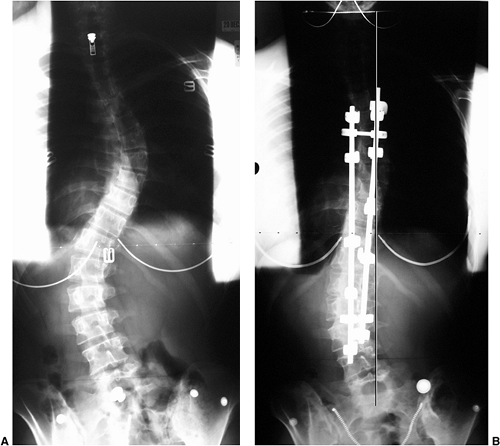

Figure 18.1 A:

This 16-year-old girl with severe scoliosis refused early treatment and had severe progression. Her clinical examination demonstrated marked trunk and rib deformity, and she had reduced pulmonary function. B: The posteroanterior radiograph demonstrates a right thoracic curvature of 125 degrees. With proper diagnosis and early treatment, deformity such as this should be completely avoidable in AIS.  |